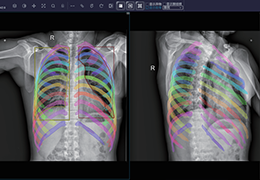

ART-Plan™ Artificial Intelligence Contouring